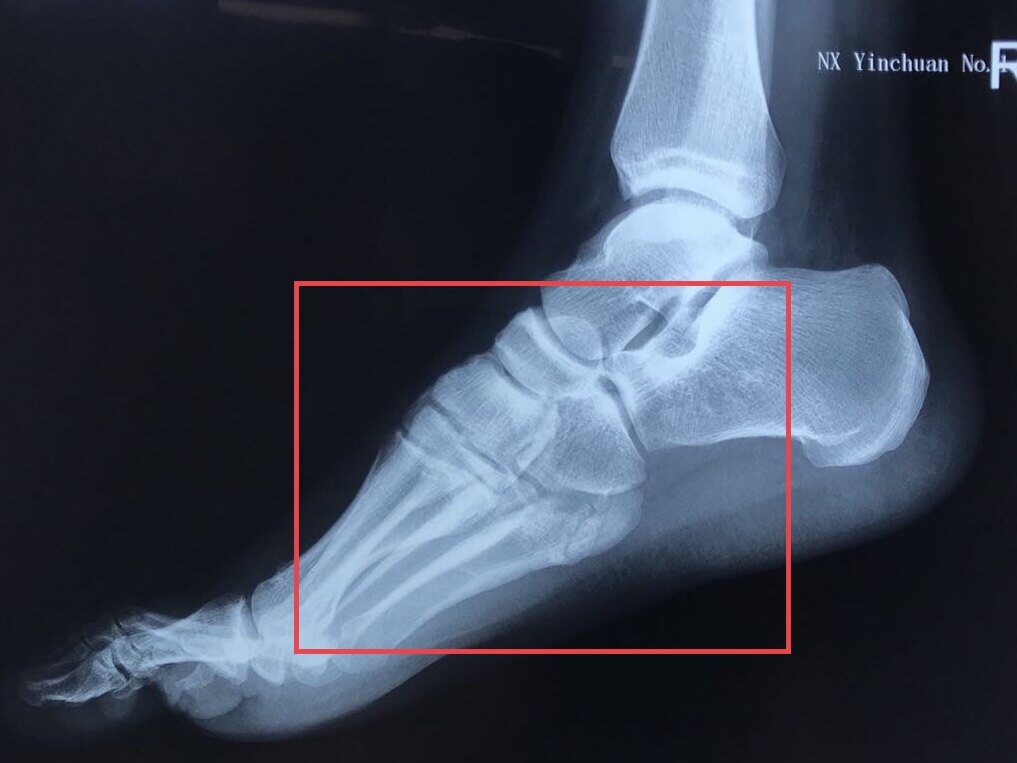

他院受診し、第5中足骨骨折と診断。 1ヶ月半以上経過するが、骨折部がズレ、骨癒合が望めない状態。 第5中足骨骨折の治療 画像検査(レントゲン) 赤く囲んだ部分が骨折している部分です。 画像検査(mri) 赤く囲んだ部分が骨折しているところです。中足骨(足の甲)は、疲労骨折を起こしやすい部位です。 スポンサーリンク 完治までの治療期間 治療法は主に経過観察となりますが、完治までの治療期間は、6週間~10週間はかかるとされています。 痛みがある場合、痛みは2週間~3週間もすれば 「第5中足骨骨折」治療と予防法 by 県境なき医師 七瀬 3月 22, 19 「足に違和感があるから整形外科に行ったら"下駄履き骨折"と言われた」「第5中足骨を骨折してしまったが、競技に復帰できるか不安」と思っている人もいることでしょう。

第5中足骨基部骨折 Jones骨折 外傷性および疲労性骨折が難治性である理由 古東整形外科 リウマチ科